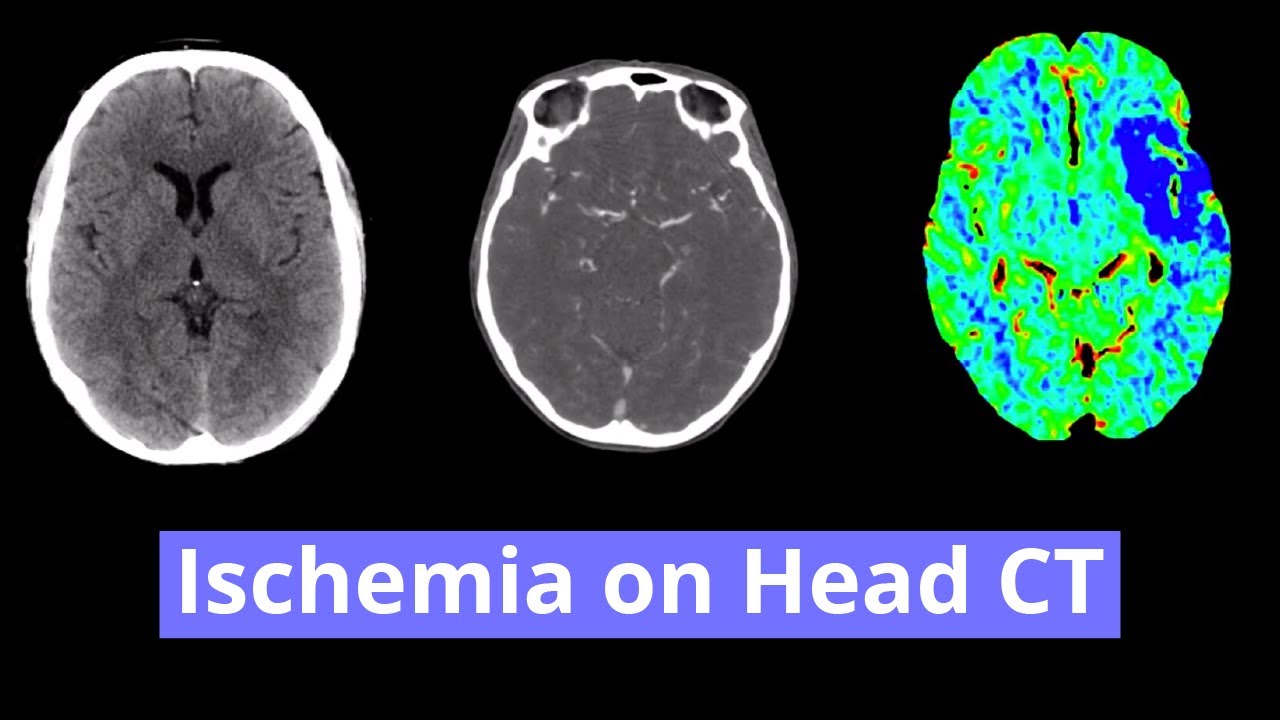

- Hypoattenuation throughout the left MCA territory with loss of gray-white differentiation and sulcal effacement

- Left MCA territory infarct

Hypoattenuation throughout the left MCA territory with loss of gray-white differentiation and sulcal effacement, compatible with early subacute ischemia. Slight left to right midline shift without evidence of herniation. No evidence of hemorrhagic transformation.

- The MCA territory is by far the most common affected by ischemia

- The deep gray structures and insular cortex develop cytotoxic edema quicker (usually within a few hours) than the frontal, temporal, and parietal cortical gray matter because there is more developed surface cortex collateral flow, so look closely at the basal ganglia and insular cortex (e.g. insular ribbon sign, which is loss of gray-white differentiation between the insular cortex and external capsule)